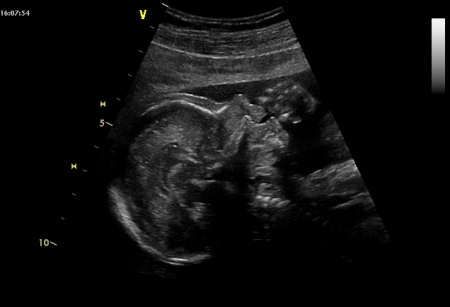

Po celé toto období pokračuje růst těla dítěte i jeho jednotlivých částí. Vyzrávají vnitřní orgány, které pokud již nefungují, připravují se na činnost po porodu. Miminko je v tomto období již v pohybu značně omezeno, v děloze zaujímá typickou polohu, hlavička je ohnutá a bradička se dotýká hrudníku. Ohnutá jsou i zádíčka a končetiny. Ručičky jsou ohnuty v loktech a jsou překřížené na přední straně hrudníku. Dolní končetiny jsou ohnuty v kyčlích i v kolenou, holeně jsou překřížené na přední straně bříška. Tomuto uspořádání se říká pravidelné držení plodu.

Plod měří od temene k zadečku asi 33 cm, váží asi 2500 g.

Maminka se v 35. týdnu těhotenství snadno zadýchá, a to i v klidu, děloha totiž tlačí zespod na plíce v hrudníku, vrchol dělohy dosahuje nejvýše z celého těhotenství. V dalších týdnech rozvolněním děložního hrdla mírně klesne. Ruku v ruce s dechovými obtížemi může maminku trápit také pálení žáhy v důsledku tlaku dělohy na žaludek a zpětném pohybu natrávené stravy i se žaludečními kyselinami do jícnu. U miminka vyzrávají všechny orgány a připravují se na svou funkci po porodu. Miminko již váží dvě a půl kila a v děloze zaujímá typickou polohu s ohnutou hlavičkou, bradou na hrudníku a ohnutými končetinami ve všech kloubech. Horní končetiny jsou tak položeny na hrudníku, dolní na přední straně bříška. V poslední době se množí diskuze o porodu císařským řezem. Rozhodně není rozumné jej žádat v případech, ve kterých to není potřeba. Jako každá operace má i císařský řez svá rizika, břicho po ní bývá velmi bolestivé a hojí se 6 týdnů, kdy by se žena neměla namáhat, kojení po něm nastupuje o pár dnů později. JM